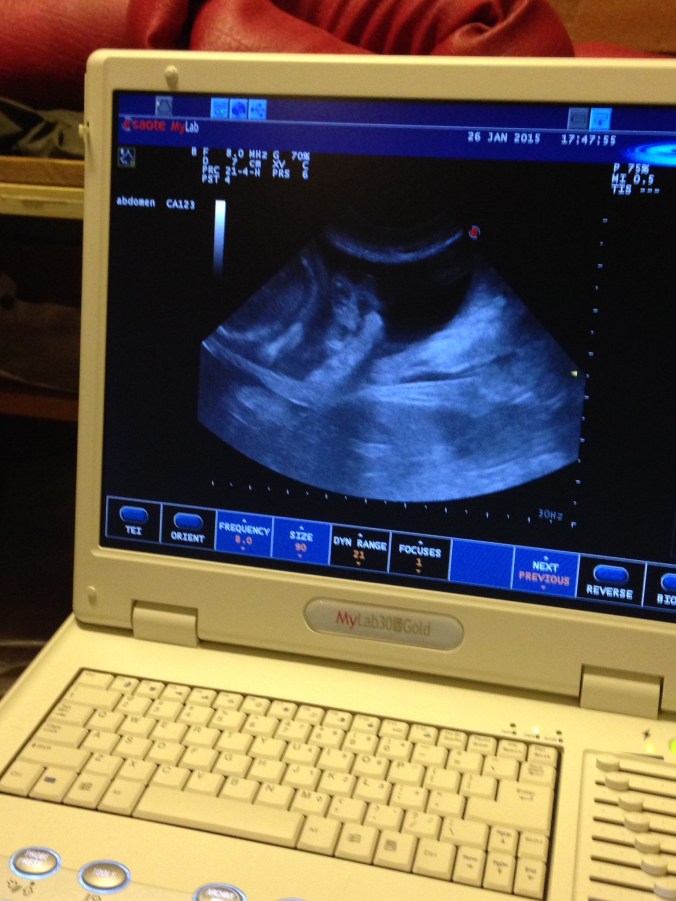

Var på ultralyd med Bonnie mandag 26/1.

Ser ut til og bli mange kvelpar, truleg 6 eller 7.